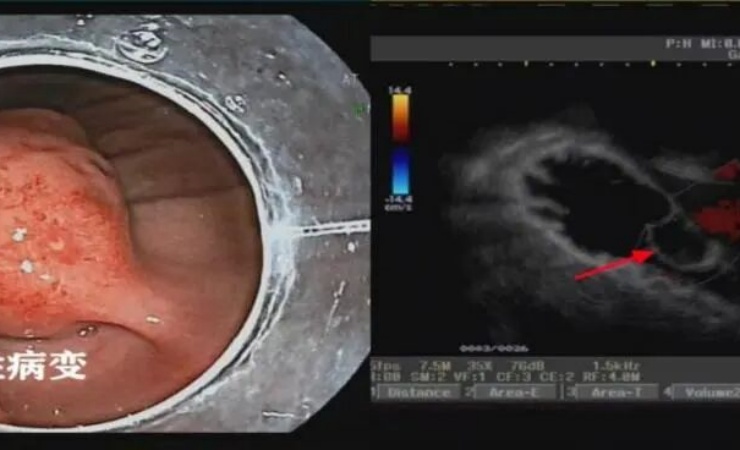

临床中胃肠间质瘤(gastrointestinal stromal tumor, GIST)是一种起源于胃肠道间叶组织的肿瘤,它可以发生在消化道的任何部位,以胃和小肠最为常见。是一种具有恶性潜能的肿瘤。大多数小GIST(直径<2cm)或微小GIST(直径<1cm)被认为是良性肿瘤。临床上根据肿瘤大小、原发部位和病理报告中的核分裂象数,用“极低危”、“低危”、“中危”和“高危”来评估原发胃肠间质瘤切除术后的危险度。危险度越高,复发风险越大。患者在初期时往往没有任何症状。随着肿瘤变大,患者会出现恶心、呕吐、消化道出血、腹部疼痛的症状,因此很难引起重视。

如今随着消化内镜技术的不断发展,ESD在诊疗早期的消化道肿瘤方面有不可替代的应用价值,其具有创伤小、疗效确切、并发症少、恢复快等特点。与传统手术和腹腔镜手术相比,术前准备简单快捷、手术时间短、术后护理方便,而且对于部分不能满足传统或者腹腔镜手术要求的重症及复杂合并症患者,在严密监控情况下也可进行,可再次提高患者的生存质量和生存期。已几乎或可完全代替传统的外科手术,减少了外科手术所带来的创伤。